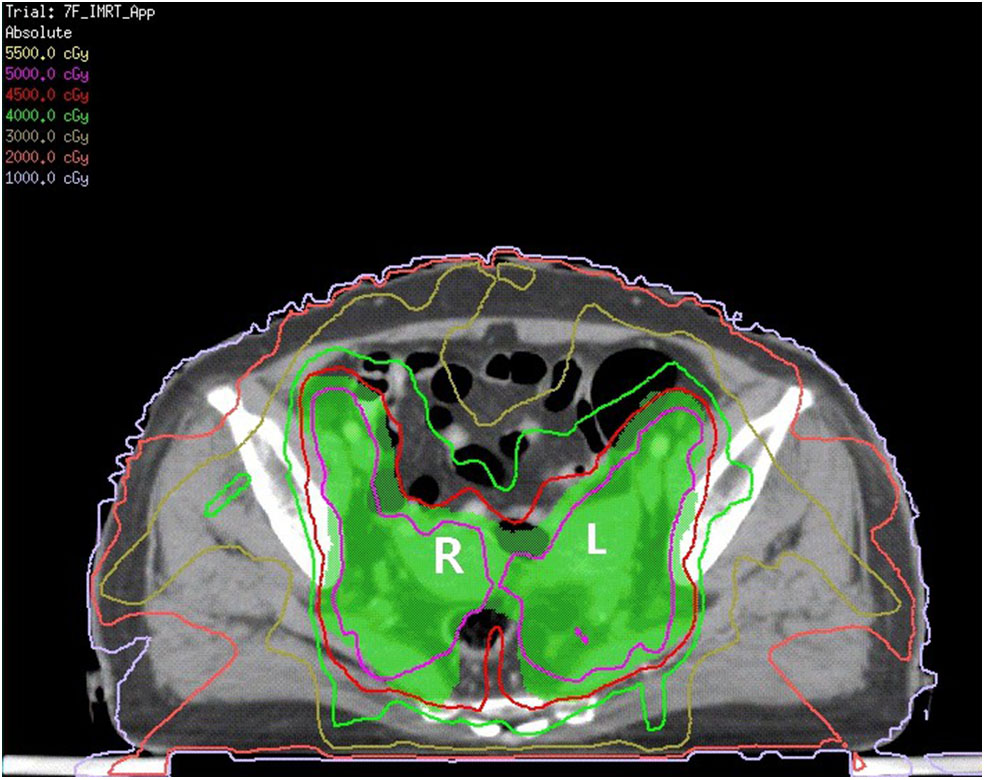

Figure 2

The green area is shown as PTV. The red line is the 4,500 cGy isodose curve. L, left uterine; R, right uterine.

The patient received neoadjuvant chemotherapy [two cycles of paclitaxel (175 mg/m2) and carboplatin (area under the receiver operating characteristic curve four)] from December 9, 2016, to January 12, 2017, followed by whole-pelvic CT-based IMRT. The clinical target volume (CTV) comprised the cervix, parametrium, uterus, upper third of the vagina, and regional lymph nodes (internal, external iliac, and common). The upper field border was at the level of the L4/L5 interspace, and the caudal field border was at the lower margin of the obturator foramen (Figure 1). Accounting for organ motion and setup uncertainty, we applied a 5-mm margin around the CTV to establish the planning target volume (PTV). IMRT planning consisted of three to seven coplanar fields with 6-mV photon beams. The prescription dose to cover 95% of the PTV was 45 Gy in 25 fractions (Figure 2). The following organs at risk were delineated: the spinal cord, femoral heads, kidneys, bladder, rectum, small bowel, and pelvic bone marrow.